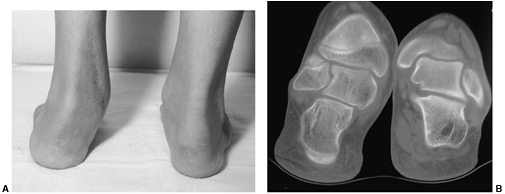

This may result from overlengthening of the heel cord and mimic the

overlengthening of the heel cord. Coleman (106) has described an osteotomy of the calcaneus in which the tuberosity is translated posteriorly. The

combined effect of this osteotomy is to decrease the calcaneal pitch

while increasing the moment arm for pull of the gastrocsoleus complex.

Clinically, patients with foot pain and weak push-off may be improved

by this operation. The author has no data on the increased strength of

the gastrocsoleus that is associated with such an osteotomy, but it

does decrease the elevation of the longitudinal arch and does relieve

some of the symptoms associated with the short cavus foot.

![]() |

Figure 30.16 A:

A weak gastrocsoleus complex may result in a “calcaneus” deformity in which the calcaneal pitch is significantly increased and the mechanical advantage of the gastrocsoleus complex significantly decreased. B, C: A calcaneal lengthening osteotomy improves foot alignment and lengthens the gastroc moment arm. |